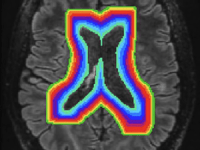

Chronic active lesions are areas of ongoing inflammation in the brain that continue to slowly grow over time. Unlike the sudden appearance of new lesions during MS relapses, these chronic lesions represent a different type of disease activity. They’re characterized by persistent chronic slow-burning inflammation at the lesion edge, which leads to gradual damage to surrounding brain tissue and axonal loss leading to brain atrophy.

Over the past decade, our lab has been at the forefront of research dedicated to understanding the role of smouldering inflammation at the rim of chronic MS lesions. This persistent, low-grade inflammation is increasingly recognised as a critical driver of disease progression, contributing to the expansion of chronic lesions and irreversible neurological damage. Our work has focused on uncovering the mechanisms behind this phenomenon, examining how lesion expansion correlates with worsening disability and progression in MS patients.

To advance this area of research, we have developed and refined cutting-edge tools and methodologies to monitor smouldering inflammation and lesion dynamics. These include advanced imaging techniques and automated pipelines for quantifying lesion expansion with high precision.

We investigated the spatial distribution of chronic lesion expansion, revealing patterns that highlight the variability and focal nature of smouldering inflammation. This work contributes to understanding the heterogeneity of lesion behaviour and its implications for disease progression.